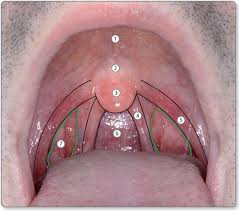

Anatomy structures hard palate palatine raphe/posterior nasal spine soft palate/velum uvula/musculus uvulae anterior faucial arches Dependent on cognition, upper extremity mobility, oral mobility, taste, smell, vision. Cold stimulation of the oropharyngeal mucosa, including the faucial pillar region, is used as a specific technique for the treatment of swallowing disorders. Pharyngeal arch muscular contributions skeletal contributions nerve artery; Pal·a·to·glos·sal arch ta one of a pair of ridges or folds of mucous membrane passing from the soft palate to the side of the tongue; The anterior faucial arches have a strong connection between the sensory receptors and nts via afferent fibers of the glossopharyngeal nerve (ix) creating a trigger point for younger adults. Faucial definition at dictionary.com, a free online dictionary with pronunciation, synonyms and translation. Two archlike folds of mucous membrane (glossopalatine and pharyngopalatine arches) that form the lateral margins of faucial and pharyngeal isthmuses. Faucial arch the examination of oral anatomy should include careful observation of lip configuration, hard palate configuration, intact nature of the faucial arches (both anterior and posterior) lingual configuration and adequacy of the sulci at the sides and front of the mandible. Sensory receptors in oropharynx & tongue & sensory recognition center in medulla reflex appears to be voluntary and reflexive phase is terminated when the bolus head passes between anterior faucial arches & tongue if there's no swallow trigger there's a delay in swallow Move medially in order to increase pressure. 1st (also called mandibular arch)muscles of mastication, anterior belly of the digastric, mylohyoid, tensor tympani, tensor veli palatini: This study was designed to quantify the effects of thermal sensitization on the oral and pharyngeal transit times of the swallow following sensitization in a group of 25 neurologically impaired patients exhibiting delayed triggering of the swallowing reflex.

The anterior faucial arches have a strong connection between the sensory receptors and nts via afferent fibers of the glossopharyngeal nerve (ix) creating a trigger point for younger adults. This video shows you how to pronounce faucial Pharyngeal transit time is defined as the time it takes for the bolus to pass from the faucial arches over the base of the tongue and through the pyriform sinus into the esophagus. The oral cavity or mouth is bounded anteriorly by the lips, posteriorly by the faucial arches just anterior to the tonsils, laterally by the cheeks, superiorly by the palate, and inferiorly by the muscular floor (fig. Dependent on cognition, upper extremity mobility, oral mobility, taste, smell, vision. Tonsils within the oral cavity. Faucial definition at dictionary.com, a free online dictionary with pronunciation, synonyms and translation. Pal·a·to·glos·sal arch ta one of a pair of ridges or folds of mucous membrane passing from the soft palate to the side of the tongue;

It is a narrow passage between the velum and the base of the tongue. Swallow reflex is triggered at base of anterior faucial arch; The tonsils are composed of lymphatic tissue and are a component of waldeyer's ring along with t … The anterior faucial pillars (afp) are bilaterally located on the oral side of the velum and form part of the soft palate. The fauces, isthmus of fauces, or the oropharyngeal isthmus, is the opening at the back of the mouth into the throat. Sensory receptors in oropharynx & tongue & sensory recognition center in medulla reflex appears to be voluntary and reflexive phase is terminated when the bolus head passes between anterior faucial arches & tongue if there's no swallow trigger there's a delay in swallow When autocomplete results are available use up and down arrows to review and enter to select. What do the faucial arches need to do during the pharyngeal stage and why?